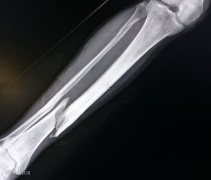

藕纤维支架的出现,为骨折治疗带来新希望。藕,这种常见食材,内部有独特的多孔结构,其纤维具备良好韧性与生物相容性。科研团队正是看中这些特性,通过一系列复杂技术手段,将藕纤维提取并加工成适合人体的支架。

其一,它具有良好生物相容性,能与人体组织和谐共处,大大降低排异风险;

其二,多孔结构有利于细胞附着、增殖与分化,宛如为细胞提供一个个温馨 “家”,加速骨折部位愈合;

其三,藕纤维支架在体内可逐渐降解,无需二次手术取出,避免患者再次遭受手术之苦。

目前,藕纤维支架在动物实验中已取得显著成果。实验表明,植入藕纤维支架的骨折动物,骨折愈合速度比传统治疗方法快近三分之一,且愈合后骨骼强度与正常骨骼无异。虽然距离大规模临床应用还有一段路要走,但这一突破已让人们看到骨折治疗的新曙光。